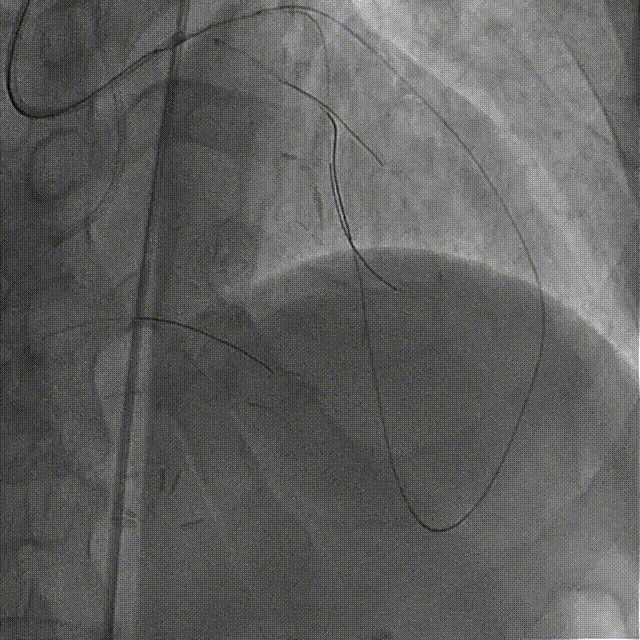

在HighTrack微导管的支撑下及逆向导丝的指引下,正向用Gaia First、Gaia Third、PILOT 200导丝反复尝试,均未能通过闭塞段进入血管真腔。

逆向重新送入一根SION Blue导丝反复尝试,最终进入正向指引导管内,推送逆向微导管至正向指引导管内,逆向送入RG3导丝至正向入口,正向沿RG3导丝推送微导管至LAD远段,撤出逆向导丝及微导管,交换一根SION Blue导丝至LAD远段。